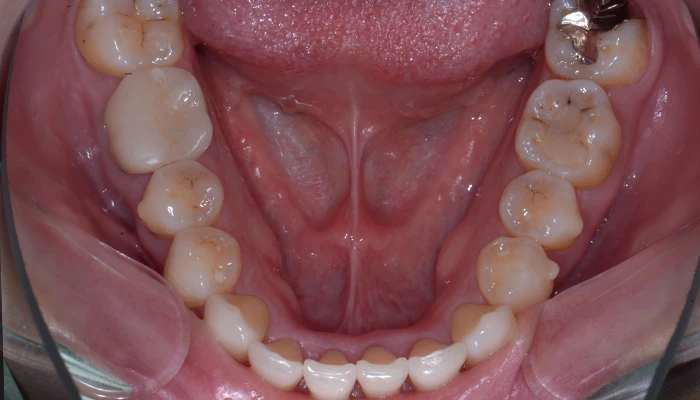

症例8. 下顎のみ部分矯正/

大臼歯近心移動

治療前

治療後

治療期間 | 18ヶ月 |

治療費 | 15万+tax (別途調整料) |